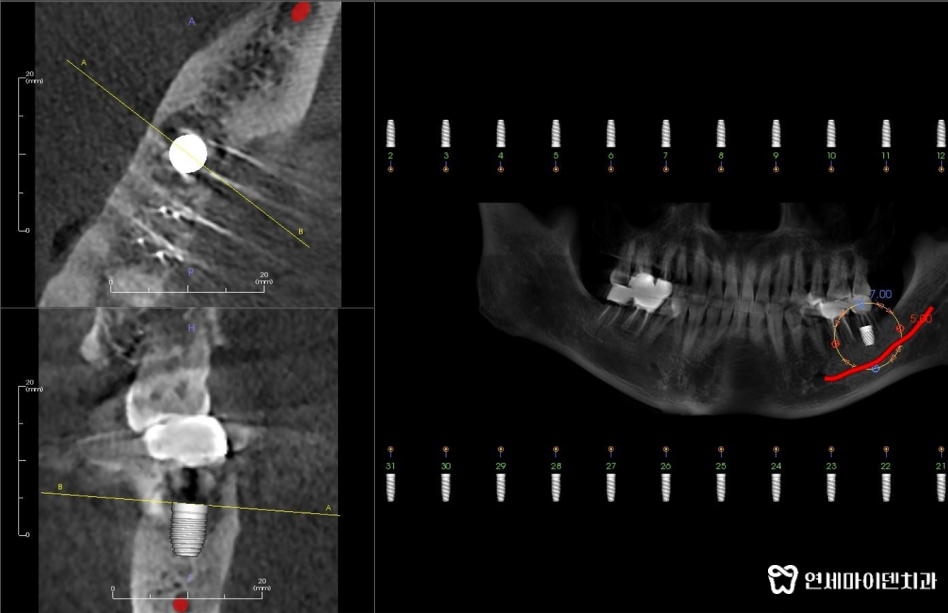

먼저 엑스레이와 CT 촬영을 진행합니다.검사를 통해 신경관의 위치와 치아 주변 뼈 상태를

꼼꼼하게 확인합니다.특히, 아래턱에 임플란트를 식립할 때에는

신경관이 지나가는 경로를 꼭 정확하게 파악해야 합니다.

만약 임플란트를 하치조 신경관에 너무 가깝게 심는다면

신경 손상이 발생할 수 있기 때문입니다.신경 손상이 발생하면 입술이나 턱 주변이 마비되거나

심한 통증을 느낄수 있어서 매우 섬세한 작업이 필요합니다.이 환자분의 경우에도 CT 촬영을 통해 신경관의 위치를 정확하게 파악했고

이를 토대로 임플란트를 안전하게 심을 수 있는 위치와

정확한 각도를 설정해주었습니다.임플란트 수술 전 치과의사의 준비 루틴

본격적인 수술에 들어가기 전에

3D 네비게이션으로 임플란트가 식립되는 위치와 깊이를 설정합니다.모의 시술로 어느 위치에 어느 깊이로 심어야 할지 디자인하면서

신경관이나 다른 구조물에 닿지 않도록 세밀하게 계획해야 합니다.여러번의 모의 시술 끝에 발치 즉시 임플란트 수술을 진행합니다.